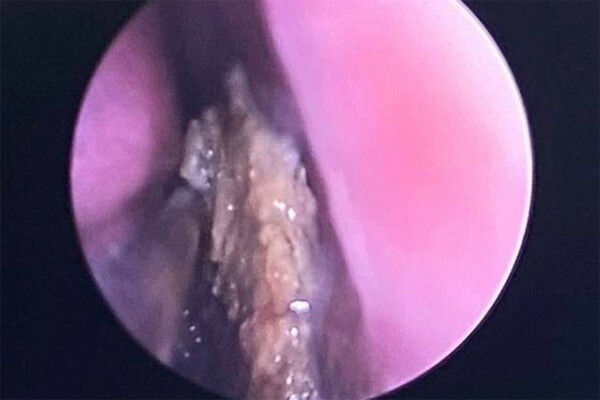

«Пациентка — одна на миллион»: врачи удалили россиянке огромный носовой камень

В Нижнекамске женщине удалили огромный носовой камень

В ГАУЗ «Нижнекамская центральная районная многопрофильная больница» обратилась женщина с жалобами на заложенность носа и гнойные выделения с резким запахом. Симптомы оказались вызваны ринолитом — образованием камня в носовой полости. Об этом сообщает Telegram-канал «Медицинская Россия».

«Многие ЛОР-врачи за всю свою профессиональную практику не встречают пациентов с таким диагнозом. О ринолите мы знаем из медицинских журналов. Обычно его обнаруживают у детей. Конечно, он бывает в разы меньше, размером с маленькую бусинку. Такой диагноз ставится одному пациенту из 10 000. В нашем случае, с таким большим камнем пациентка точно одна на миллион», — рассказал заведующий оториноларингологическим отделением Искандер Мубаракшин.

Камень мог начать образовываться у женщины еще в раннем детстве. Врачи предполагают, что в три-четыре года ей в нос попала песчинка или другое инородное тело. Это привело к повышению вязкости носовой слизи. Пациентка не обращала на это внимание, а инородное тело с годами начало покрываться минеральными солями и слизью.

Длина камня составляла 4 сантиметра, он перекрывал носовой проход. В носу пациентки появились пролежни и перфорация носовой перегородки, поэтому ей понадобилась срочная операция. Твердый носовой камень врачам пришлось расколоть бором и щипцами. Операция прошла успешно, и женщину выписали домой.